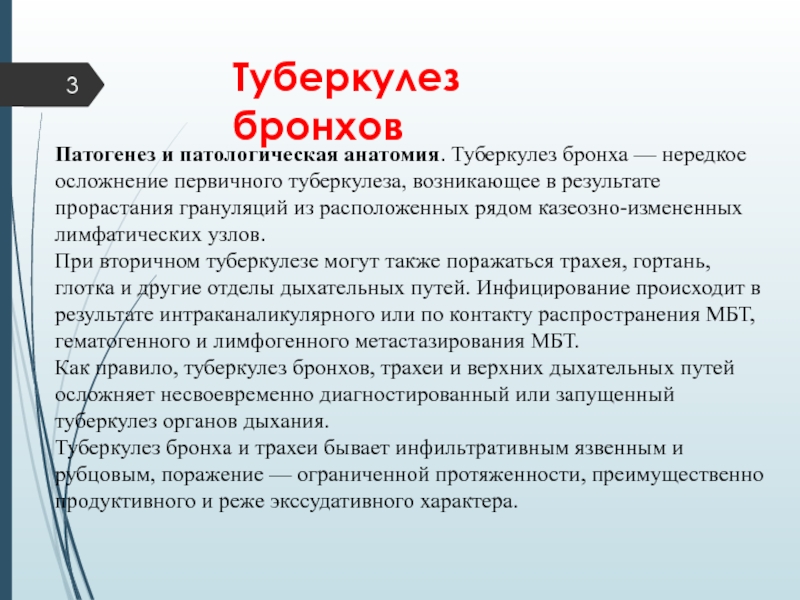

Раздел: Образы вокруг